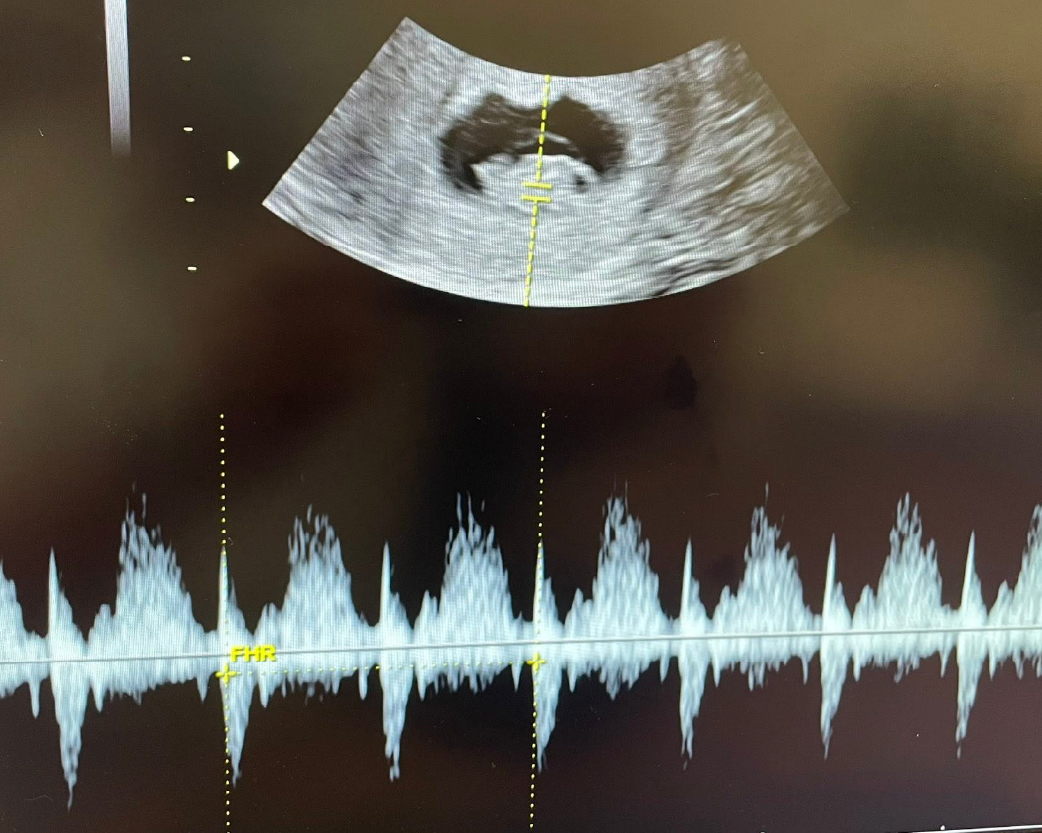

8+周胎心跳及胎兒活動力都好棒棒💕